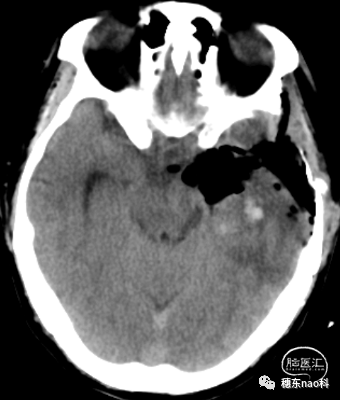

头颅增强CT提示:

左侧大脑半球大片状睡着,周边小片状高密度影,考虑胶质瘤复发,合并出血可能。